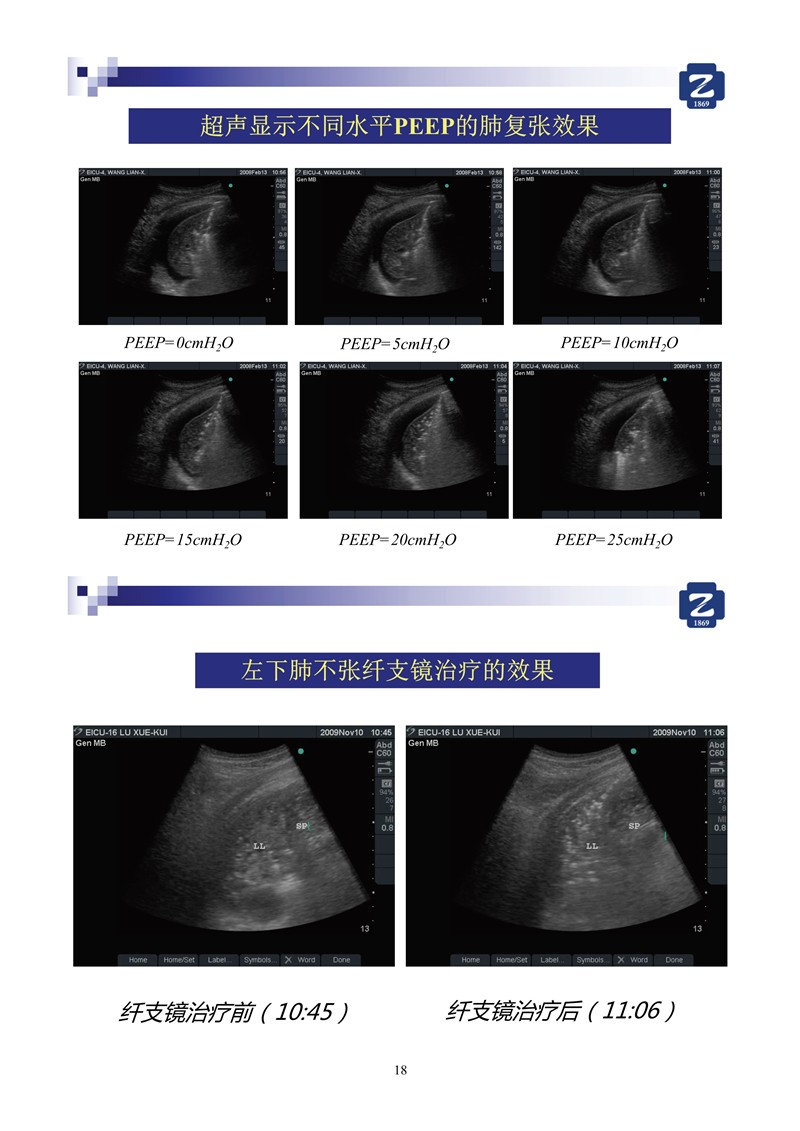

第二版新型冠狀病毒肺炎超聲診斷實用手冊(全文)